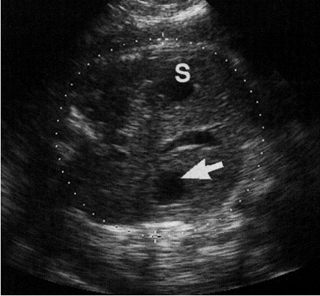

![]() |

| Εικόνα

26. Κύστη ήπατος. S: στομάχι. |

Εικόνα 27. Ηπατομεγαλία. |

Ηπατικές κύστεις

Είναι σπάνιες και προέρχονται από απόφραξη του ηπατικού χοληφόρου συστήματος.

Είναι μονόχωρες και ασυμπτωματικές, παρόλο που μπορεί να υπάρξουν επιπλοκές,

όπως φλεγμονή ή αιμορραγία (εικόνα 26).

Στο 30% των περιπτώσεων των πολυκυστικών νεφρών ενήλικα τύπου, συνυπάρχουν ηπατικές